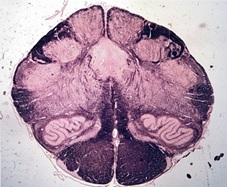

Tracts and Nuclei

Please click one of the following photos to enter the respective section.

Section #3